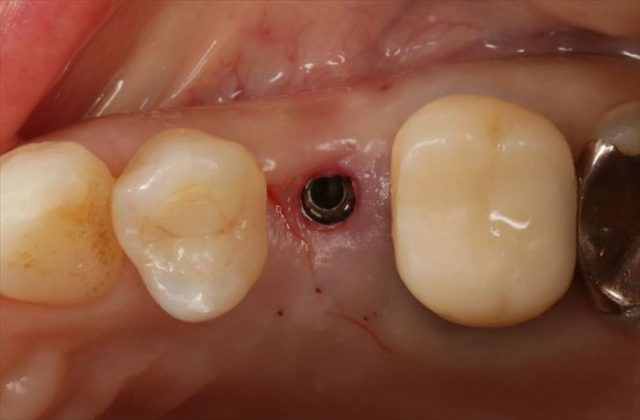

埋入を終えました。青いパーツは埋入時用のジグです。

咬合面観です。

近遠心幅が狭いのでポジションの位置決めには緊張します。

挿入ジグを外しました。

封鎖スクリューでインプラントフィクスチャーを保護します。

フラップレス埋入オペでは出血もあまりありません。

無事に終わりました。